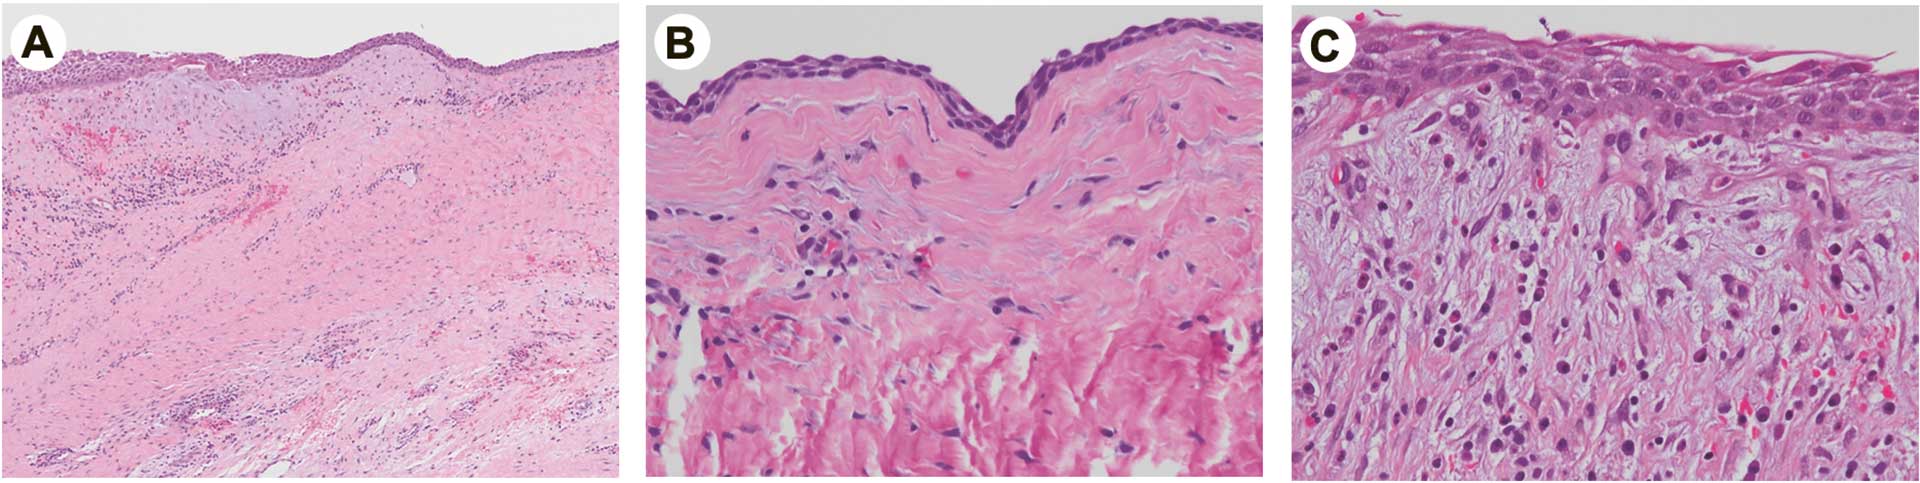

Mikroskopisk viste den første biopsien kun et fibrøst bindevev uten tegn til inflammasjon. Det ble også funnet svakt basofile finfibrede områder slik det er vanlig i follikkelvegger. Det ble imidlertid ikke funnet epitel, så man kunne ikke bekrefte den kliniske diagnosen av en follikulærcyste.

Mikroskopi av operasjonspreparatet derimot viste en plateepitelkledd cystevegg med fokal områder med mild infiltrasjon av kroniske betennelsesceller (figur 4). Dette er forenlig med en follikulærcyste. Inflammasjonen kan skyldes den tidligere biopsitakingen. Det var ingen tegn til keratinisering som i en parakeratiniserende odontogen keratocyste.

Figur 4. Histologiske foto av preparat som ble fjernet ved operasjon i oktober 2024. Bildeserien illustrere diversiteten som kan observeres i cysteveggen i en og samme cyste. A: Mikrofoto med 2x objektiv av cysteveggen. Man ser et tynt lag av flerlaget plateepitel øverst. Det hviler for det meste direkte på et fibrøst bindevev med ubetydelige tegn til inflammasjon (Venstre side). Mot høyre er epitelet noe tykkere og her ser man en mild diffus infiltrasjon av betennelsesceller. B: Mikrofoto med 20x objektiv. Et tynt epitel, nærmest toradet kubisk epitel sees øverst. Det er lik det reduserte epitel man ofte ser dekker en follikkelvegg uten cyste. Det sees kun ubetydelige tegn på inflammasjon (runde cellekjerner). C: Mikrofoto med 20x objektiv av område med mild infiltrasjon av kroniske betennelsesceller (runde kjerner). Man ser også en noe forøket epiteltykkelse som vel skyldes inflammasjonen.